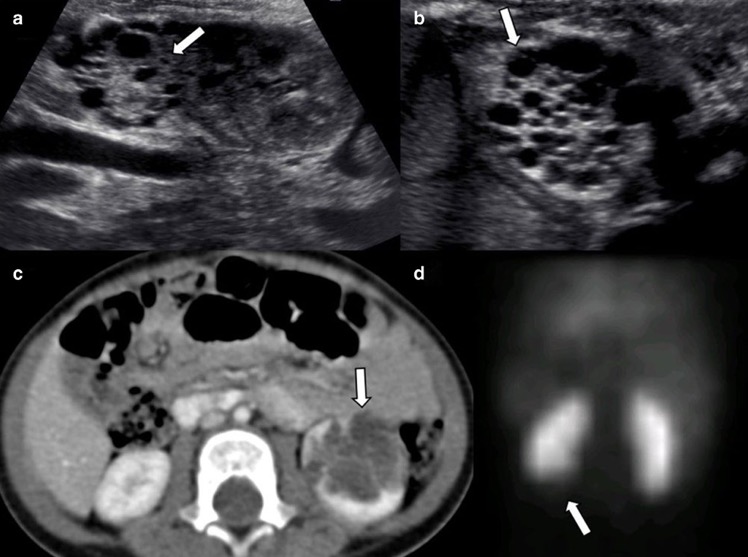

- Kyste hydatique rénal